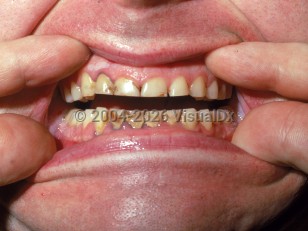

Clinical presentations are variable and dependent on patient age and severity of poisoning, but they generally include peripheral neuropathy, encephalopathy, anorexia, albuminuria, anemia, headache, hypertension, insomnia, irritability, tremor, weight loss, and gastrointestinal symptoms.